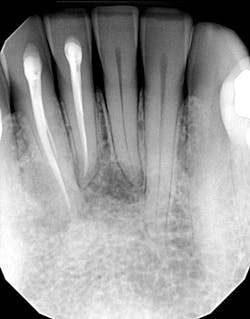

At her visit with me, the updated radiographs showed the presence of multilocular radiolucencies in the lower anterior area.Diagnosis and discussion

The patient was referred to an oral surgeon who performed curettage on the lesions and sent the tissue off to pathology. This was the attending pathologist’s report:

“…based on the morphology, I favor lateral periodontal cyst, although recurrences are more typical of the polycystic variant termed botryoid odontogenic cyst. I note that there is a reported ‘history of glandular odontogenic cyst in the same location,’ highlighting the well-known challenge differentiating lateral periodontal cyst from glandular odontogenic cyst…both lateral periodontal cyst and odontogenic keratocyst are believed to be derived from dental lamina. Clinical follow-up is recommended to ensure resolution of the radiographic abnormality.”